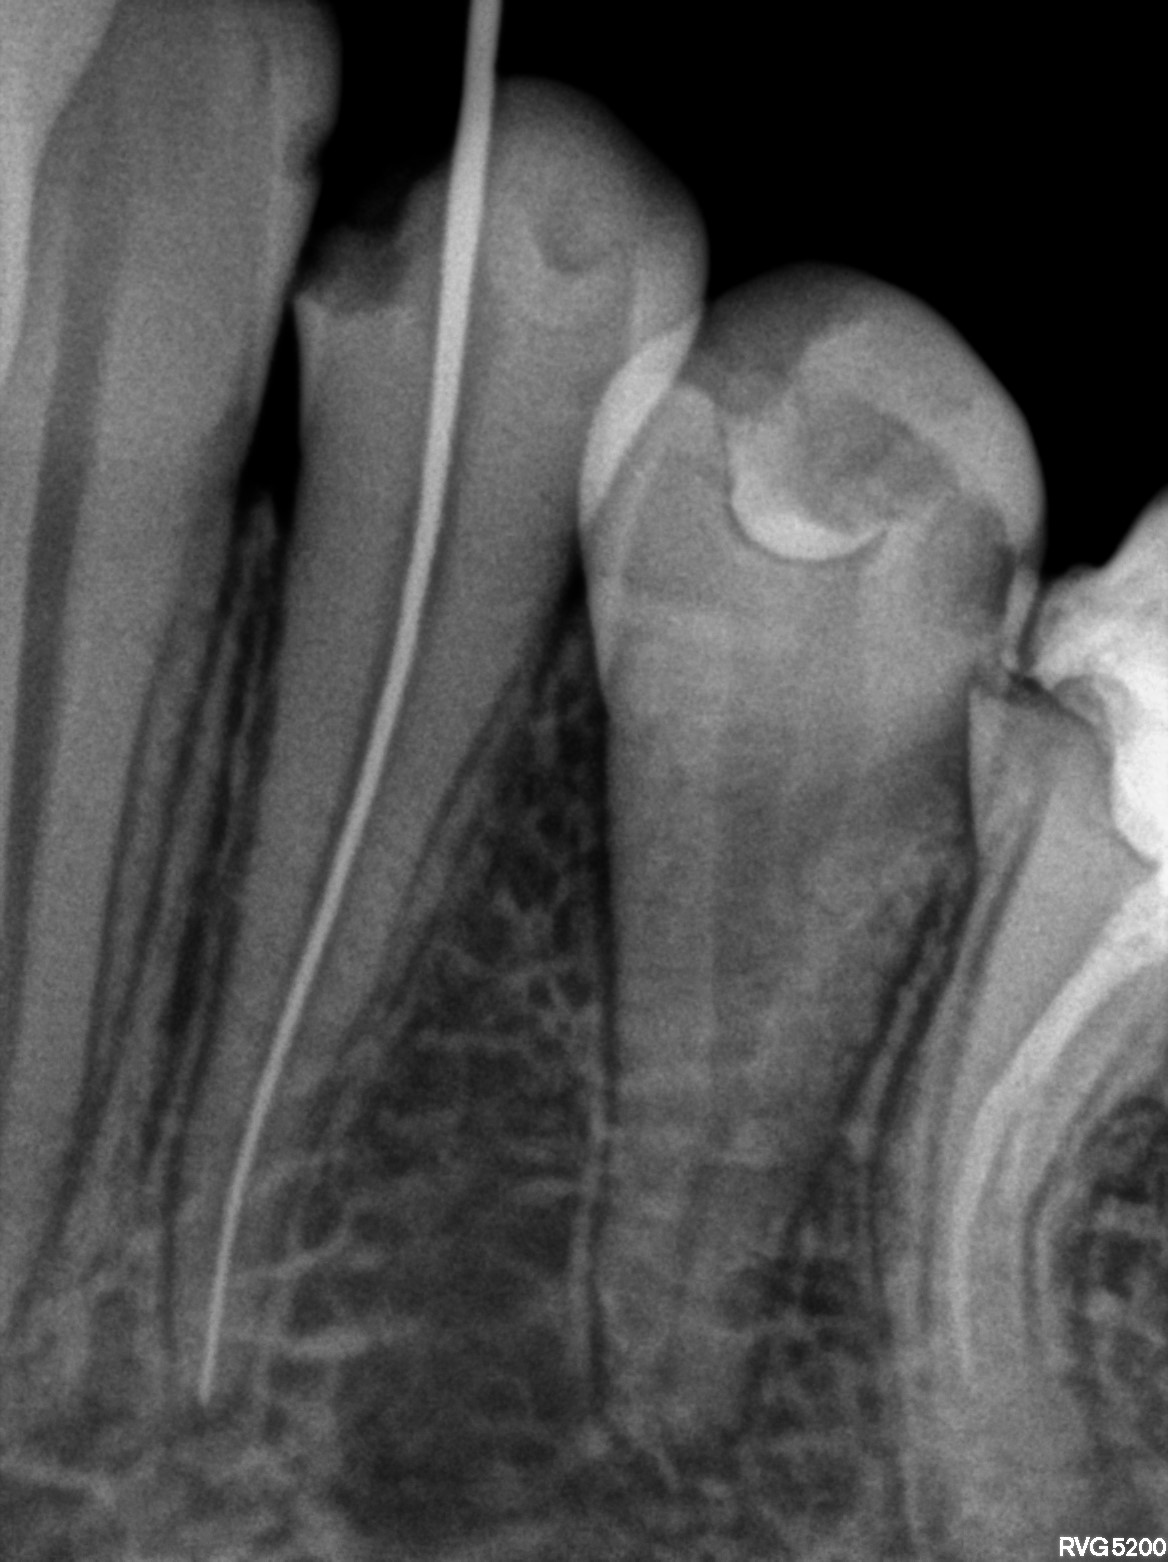

Dental Radiographs FHIR: DocumentReference · LOINC 24641-7

R61.jpg

24641-7